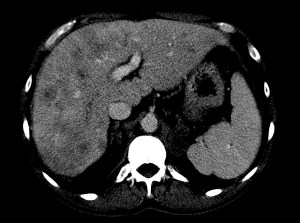

Paciente de 59 años con antecedentes personales de Cá de vejiga.

Se le realiza una Uro-Tc por seguimiento al año, aunque en esta ocasión el paciente refiere episodio de hematuria.

Tras el tratamiento de la recidiva y nefrostomía para la hidroureteronefrosis, vuelve acudir al hospital a los 9 meses por episodio de dolor en FD y malestar general. Se realiza una ecografía de urgencias.

Se realiza nueva TC bifásico abdominopélvio y Uro TC.

- Paciente con numerosas recidivas por Cá vejiga.

- Ha desarrollado un tumor metacrónico en pelvis renal derecha, también responsable de la hidroureteronefrosis.

- Mala evolución radiológica del proceso a expensas de metástasis pulmonares y hepáticas.